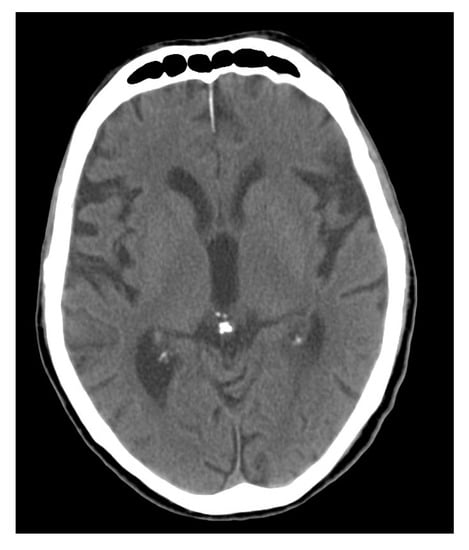

- Kiroğlu, Y.; Çalli, C.; Karabulut, N.; Oncel, C. Intracranial calcifications on CT. Diagn. Interv. Radiol. 2010, 16, 263–269. [Google Scholar]

- Doyle, A.J.; Anderson, G.D. Physiologic calcification of the pineal gland in children on computed tomography: Prevalence, observer reliability and association with choroid plexus calcification. Acad. Radiol. 2006, 13, 822–826. [Google Scholar] [CrossRef] [PubMed]

- Winkler, P.; Helmke, K. Age-related incidence of pineal gland calcification in children: A roentgenological study of 1044 skull films and a review of the literature. J. Pineal Res. 1987, 4, 247–252. [Google Scholar] [CrossRef]